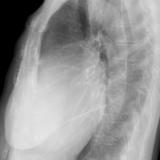

Ao tissue valve (lat only

Date: 01/26/2009

Views: 2976